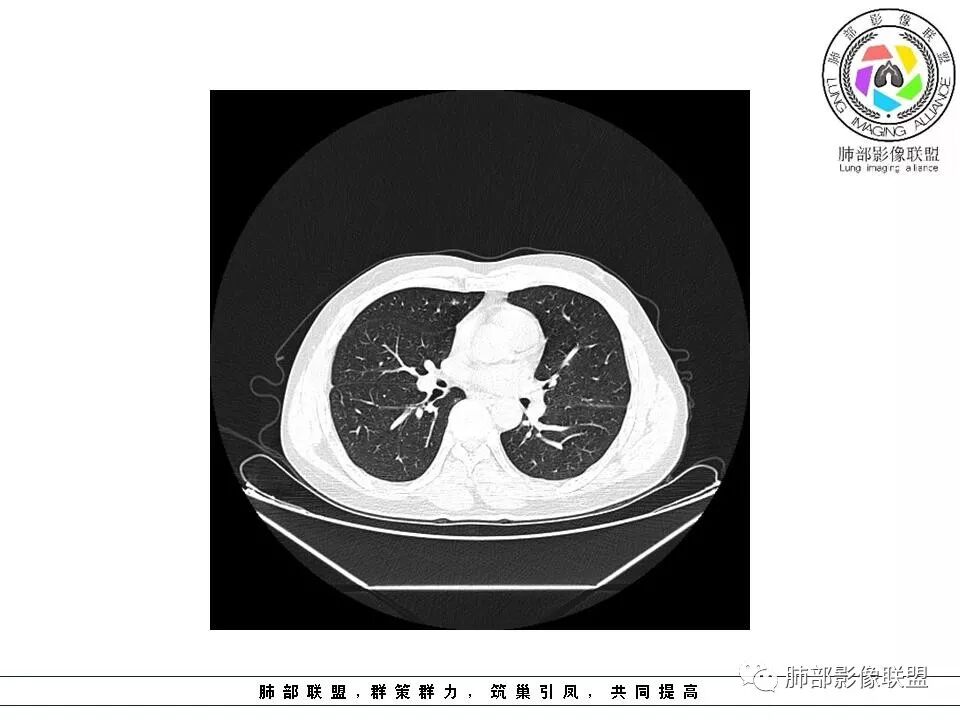

群内讨论

杨泽锋:很难通过一次CT检查来判断小结节的性质炎性结节可能大理由:病灶很小但是很密实毛刺比较长百事可乐:右肺中叶内侧段实性小结节,毛刺、分叶,胸膜牵拉。考虑MIA。李:实性结节,形态不规则,考虑炎性肉芽肿紫气东来:右肺中叶实性结节,毛刺分叶,考虑恶性。穿越七海的风:右肺上叶近胸膜下小结节,实性度较高,肺内淋巴结吧,可随访观察张帅:晨读,右肺上叶前段小结节病变,病灶内可见细支气管穿过,局部血管略增粗,病灶边界清,可见软毛刺,3月胸CT较2月貌似密度减低,毛刺变小,考虑良性病变,炎性病变?春秋:患者51男性,右上叶前段结节,形态不规整,明显分叶,前后变化不明显,考虑恶性!Yiren  Sishui(厶水伊人):小结节,密度较实,有多条线状影,胸膜下分布,肺内淋巴结?炎性肉芽肿?建议随访。东哥:晨读:右肺上叶小结节,不规则,可见分叶,整体收缩,两次CT变化不明显,先考虑良性可能我心飞翔:右上肺实性结节,长毛刺,考虑良性病变王秀仙:晨读:右肺上叶结节,边缘毛刺,一个月后,病灶略有增大,边缘小叶间隔阻挡,考虑腺癌。Shelia🌞:晨读,右肺上叶前段胸膜下小结节,形态不规则,以平直收缩为主,可见u型凹陷,长毛刺,1月复查感觉变化不大,考虑炎性病变,建议继续随访复查除外腺癌一切∮随缘:晨读病例:     右肺上叶前段可见一不规则结节,边缘可见分叶,毛刺,清晰的GGO,近端牵拉血管树,未见明显支气管截断,中年男性,体检发现,综合考虑微浸润腺癌,待排炎性肉芽肿,建议短期随访。

Ao..葉偲雨!👑:右肺中叶内侧段小结节,边缘毛刺,部分层面平直,第二次复查有凹陷,密度似乎比之前淡泊一点(肿瘤的生长周期一个月一般不会有太多变化),大小范围基本稳定,LU-Rads 4a类,炎性结节可能,建议3个月后复查或pet

南边:51岁男性,体检发现右肺结节这个年龄段的男性,啥都可以发生,也属于肺癌的高危人群南边:首先是实性还是GGO?好像实性吧

如果实性病变,边缘收缩,可以考虑炎性, 但是边缘有边界清楚GGO,一定要警惕恶性,还有粗短毛刺更要小心撇开其它,看到这个图,除非你怀疑假象,不然就是要考虑腺癌的可能

边界清楚GGO,短毛刺,这要小心瘢痕癌可以多为腺癌复查没变化,与血供有关,属于休眠期张国祯教授的理论:腺瘤样增生、原位癌都属于偏良性,就是没有侵袭性;以后发展——侵袭可以,不变可以,部分可能还会凋亡(比较少)

结果

原位腺癌